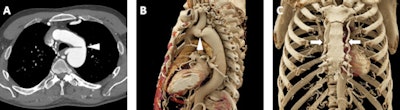

A 65-year-old man with a history of chronic thromboembolic disease. A and B: Axial postcontrast 2D CT images demonstrating eccentric filling defects in dilated left lower lobe pulmonary arterial branches (white arrowheads) compatible with chronic pulmonary embolism. C and D: Volume-rendered images demonstrate the dilated lower lobe pulmonary arteries (white arrowheads), although the eccentric filling defects from the clots are not well seen on these images. E and F: Cinematic rendering images (F is a blown up detail from E) again show the dilated lower lobe pulmonary arteries (white arrowheads), but due to the higher detail of cinematic rendering, there is a subtle textural change in the left lower lobar pulmonary artery (best seen in F) that is consistent with the patient's chronic pulmonary embolism.